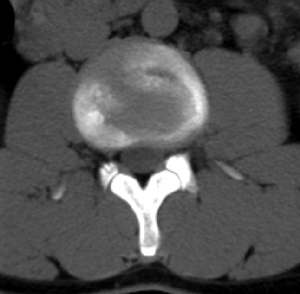

男,20,士兵,腰痛3年多,无外伤史

倒数7~9幅图像示椎体后缘双边征及双关节征,支持l5轻度滑脱。

1、多发许莫氏结节。

2、腰5双侧椎弓峡部崩裂并i度前滑脱,楼主椎间盘扫描角度有问题,另外需要反倾角扫描腰5椎弓峡部。

2、腰5双侧椎弓峡部崩裂并i度前滑脱。